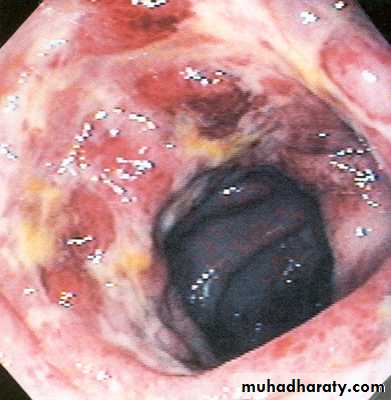

http://library.med.utah.edu/WebPath/TUTORIAL/AIDS/AIDS021.htmlCMV colitis

The transplanted organ is particularly vulnerable as a target for CMV infectionPatients may present with diarrhea, heartburn, odynophagia

Diagnosis made with biopsies obtained on endoscopy

CMV immunostain positive

IV Ganciclovir